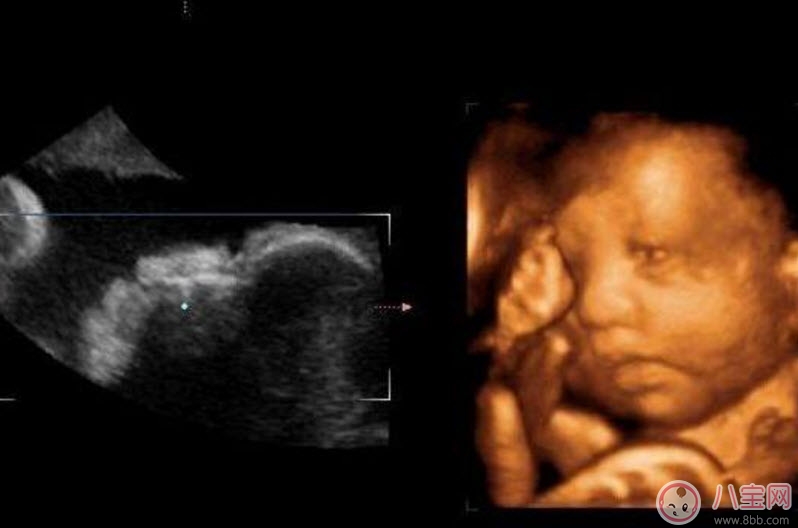

什么是四维彩超四维彩超的全称是四维彩色超声诊断仪 , 是世界上最先进的彩色超声设备 。四维彩超能够表面成像 , 可以更佳清晰的查出来胎儿的四肢发育是否畸形 , 脑膜膨出 , 是否唇腭裂、脊柱裂等先天畸形 , 及早发现及早的做出解决方案 。

二维三维四维超生的区别二维超声可以理解为我们通常说的B超 , 显示的是断面图像 。何为断面图像?就是把西瓜切开 , 你在屏幕上只能看到西瓜的切面(断面) , 但经验丰富的你 , 可以只看这个切面(断面)就知道这是一个西瓜 。

三维、四维超声就是把很多个二维断面图像通过计算机重建成一个立体的图像 。相当于把切成很多片的西瓜 , 重新堆叠成一个完整的西瓜 , 这个堆叠过程由计算机完成 。三维、四维的区别在于 , 三维是照片 , 四维是影片 , 四维就是会动的三维照片(实时三维) 。